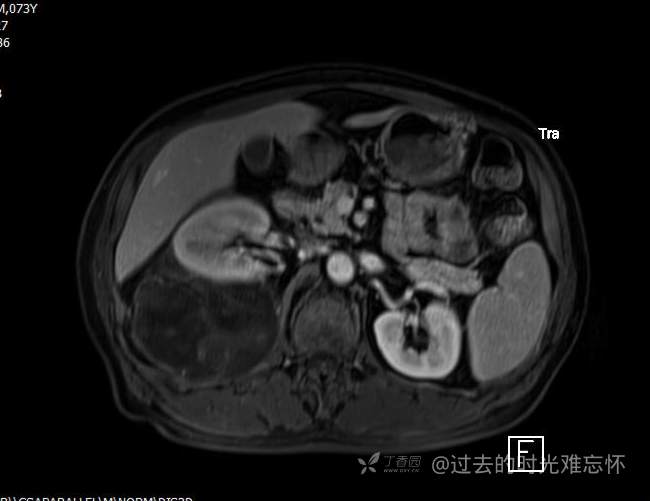

患者性别:男

患者年龄:73岁

主诉:咳嗽1月余。曾有血尿一次。后背部酸痛不适1-2年左右,无明显消瘦。

辅助检查:CT MRI

临床诊断:占位

治疗经过:手术

T2压脂